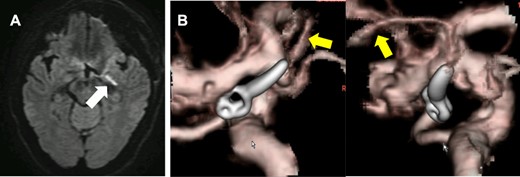

The authors were able to determine that the perforating branches originating from the dome could be sacrificed and therefore allowing complete neck clipping. And MEP did not change until skin was closed (Fig. 3). Although postoperative diffusion-weighted images (DWI) on magnetic resonance imaging (MRI) showed hyperintensity signals at the medial side of the uncus (Fig. 4A), the patient remained asymptomatic and was discharged home with a modified Rankin Scale of 0. Postoperative CT angiogram showed complete aneurysm obliteration and patency of the AchA main trunk (Fig. 4B).

DWI-MRI revealed a new ischemic brain lesion at the uncus of the left AchA territory 1 day after surgical clipping (A). CTA demonstrated complete aneurysm obliteration and a healthy patency of the AchA main trunk (B, yellow arrow).